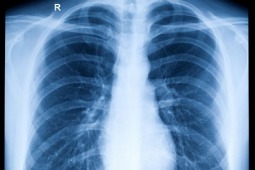

Przedoperacyjne badanie PET zmniejsza ilość niepotrzebnych operacji raka płuca o połowę

Najnowsze analizy statystyczne wskazują, że przedoperacyjne badanie PET zmienia postępowanie z pacjentami aż w 50% przypadków.